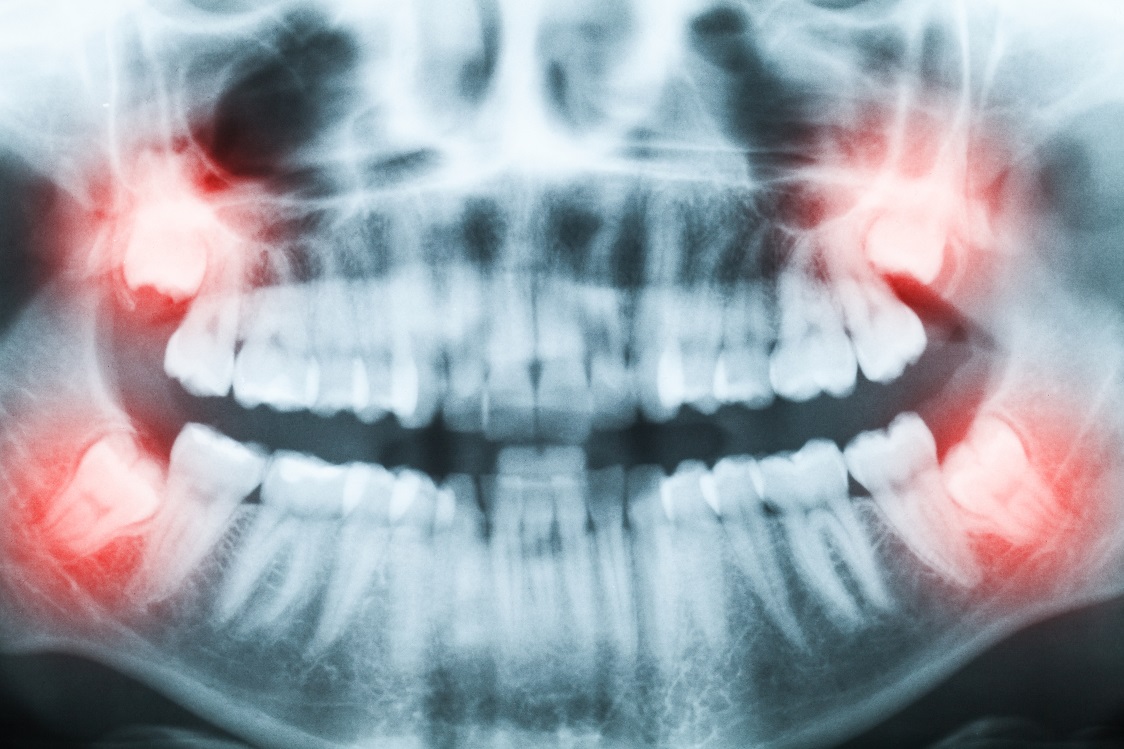

The first step to any dental procedure, especially one that may involve oral surgery is to have a consultation. During the consultation session, a diagnosis is set up of your oral condition, and x-rays are made. These are needed because wisdom teeth frequently have irregular growing patterns and irregular tooth roots, which means that the dentist has to know ahead of time what is under the gum line, before extraction begins, to ensure that the nerves and other teeth will not be affected. The consultation session is also necessary so you get to know the dentist and can ask any and all questions you may have regarding treatment.

Extraction sites have a high propensity to become infected or otherwise colonized by bacterial life. To prevent this from occurring, some preliminary treatments, like fillings, root canals or removal of plaque and a hygiene session may be necessary before the wisdom tooth extraction begins. The extraction is ALWAYS preceded by a consultation session, in which x-rays are made and analyzed, and the best course of action is decided upon, only afterwards can the wisdom tooth extraction occur.